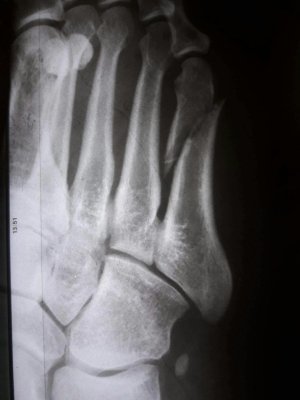

Здравствуйте. Мне 38 лет. Перелом 5-ой плюсневой.

Приложенные снимки - на следующий день после случившегося. Сразу в гипс на 5 недель. Ни в травмпункте, ни в поликлинике лечащий врач даже на упоминали операцию.

Только в травмпункте доктор сказал "... с незначительным смещением, поэтому просто гипс на месяц."

Посмотреть вложение 13116 Посмотреть вложение 13117